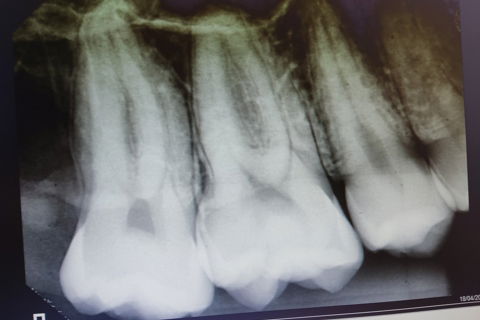

18 antes

rx 18 pos